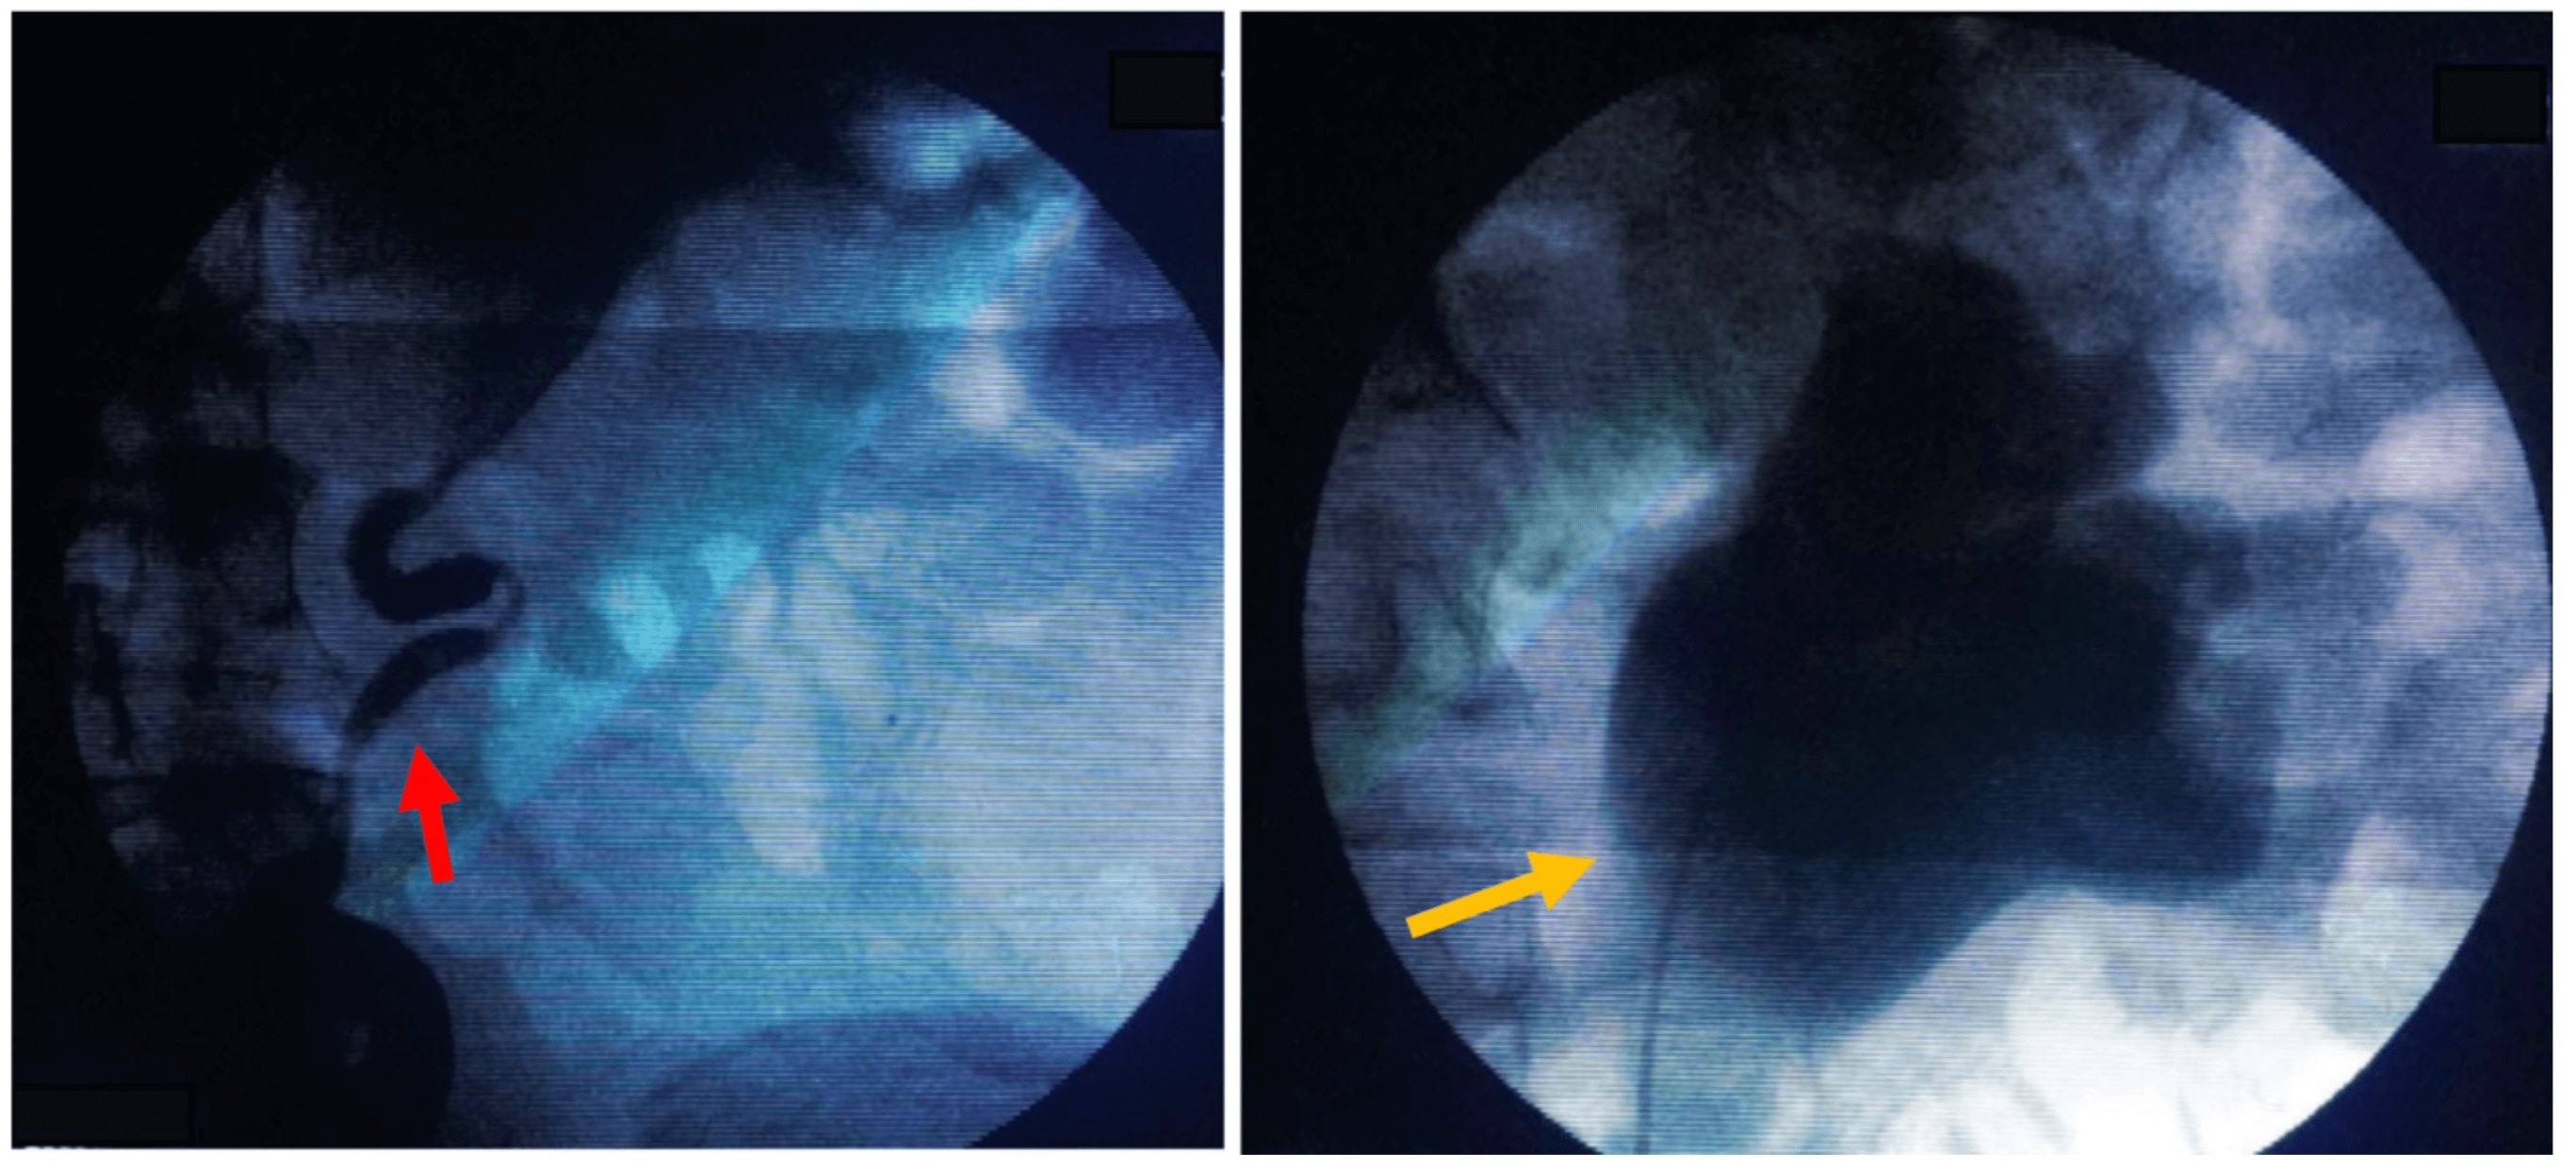

Paciente masculino de 76 años previamente asintomático y sin enfermedades de base que asiste a consulta externa de urología refiriendo aumento del contenido escrotal. Al examen físico presenta hidrocele bilateral, de predominio derecho, testículos bilaterales normotróficos sin masas, próstata de consistencia aumentada, no dolorosa. Se indica realizar hidrocelectomía y se solicita un antígeno prostático específico (PSA). Posteriormente acude a urgencias por supuración en hemiescroto derecho, asociado a fiebre, pérdida de peso y dolor testicular que no mejoró con manejo antibiótico ambulatorio. Se realiza examen físico al paciente, comprobándose su regular estado general; presenta taquicardia, deshidratación y carencia de áreas de drenaje escrotal, sin zonas crepitantes o de necrosis. Se inicia manejo antibiótico intravenoso y se solicitan paraclínicos, evidenciando leucocitosis con neutrofilia, uroanálisis con piuria estéril y elevación de azoados. La ecografía testicular no presenta hallazgos sugestivos de colecciones a nivel escrotal, por lo que se descarta el diagnóstico de absceso escrotal. Por el cuadro infeccioso a nivel escrotal se decide realizar hidrocelectomía derecha, evidenciando drenaje de aproximadamente 100 cc de líquido cetrino con epidídimo derecho engrosado caliente al tacto, el cual se punciona y drena material caseoso y purulento. Testículo derecho indurado sin áreas evidentes de secreción, por lo que se decide realizar epididimectomía derecha (Figura 1). Por hallazgos intraoperatorios de material caseoso y purulento, testículo indurado y sin foco infeccioso aparente, se sospecha tuberculosis genital, se solicitan estudios de patología y baciloscopia seriada para identificar bacilos ácido- alcohol resistente (BAAR). Se da egreso médico por adecuada evolución posoperatoria y control prioritario. El paciente consulta a urgencias a los 5 días posoperatorios con dificultad respiratoria y fiebre. Se encuentra al paciente en mal estado general, taquipneico y desaturado (saturación de oxígeno al ambiente: 85 %), requiriendo soporte ventilatorio con Venturi. La radiografía de tórax evidencia opacidades micronodulares en todo el parénquima pulmonar. Los reportes de patología y baciloscopia (BK) de epidídimo son positivos para infección por BAAR en tejido por Mycobacterium tuberculosis. Se inicia manejo tetraconjugado (Pirazinamida 1600 mg/día vía oral + Etambutol 1100 mg/día vía oral + Isoniacida 300 mg/día vía oral + Rifampicina 600 mg/día vía oral) asociado a Piridoxina 50 mg /día vía oral, por tuberculosis miliar, pulmonar y genitourinaria. Se decide solicitar ecografía de vías urinarias por la sospecha de TBCGU, evidenciando hallazgos sugestivos de dilatación pielocalicial bilateral, por lo que se solicita urografía excretora para descartar compromiso ureteral. Se evidencia retardo en la eliminación del medio de contraste bilateral asociado a dilatación ureteral bilateral de predominio derecho (Figura 2). Con estos hallazgos sugestivos de TBCGU, se realiza pielografía retrógrada bilateral (Figura 3), y por sus hallazgos se decide derivar al paciente con catéter JJ bilateral por compromiso ureteral de TBC con el fin de aliviar la dilatación pielocalicial previamente referida y evitar la progresión a falla renal. El paciente es dado de alta por infectología y urología. En el momento se encuentra asintomático con adecuados niveles de azoados.

Es de vital importancia descartar tumores testiculares e identificar que generalmente la infección por tuberculosis empieza en el epidídimo, y que se extiende al testículo de forma tardía. La epididimitis tuberculosa se presenta como un epidídimo alargado con lesiones nodulares heterogéneas e hipoecoicas. Las imágenes radiológicas no serán útiles en estadios tempranos (3,9,18). Hallazgos ecográficos de orquitis incluyen testículos hipoecoicos homogéneos o heterogéneos, o testículos alargados nodulares heterogéneos e hipoecoicos. Otros hallazgos incluyen engrosamiento de la piel escrotal, hidrocele, abscesos escrotales y fístulas (9). Por lo tanto, una lesión testicular asociada a compromiso del epidídimo y engrosamiento de la piel favorece el diagnóstico de TBCGU (6). La pielografía intravenosa está indicada en pacientes con leucocituria y anormalidades en estudios ecográficos, como en el paciente documentado, que tenía dilatación pielocalicial. La urografía excretora puede detectar signos como distorsión de los cálices, calcificaciones, estenosis de uréter y fibrosis vesical (19), como los evidenciados en este caso.